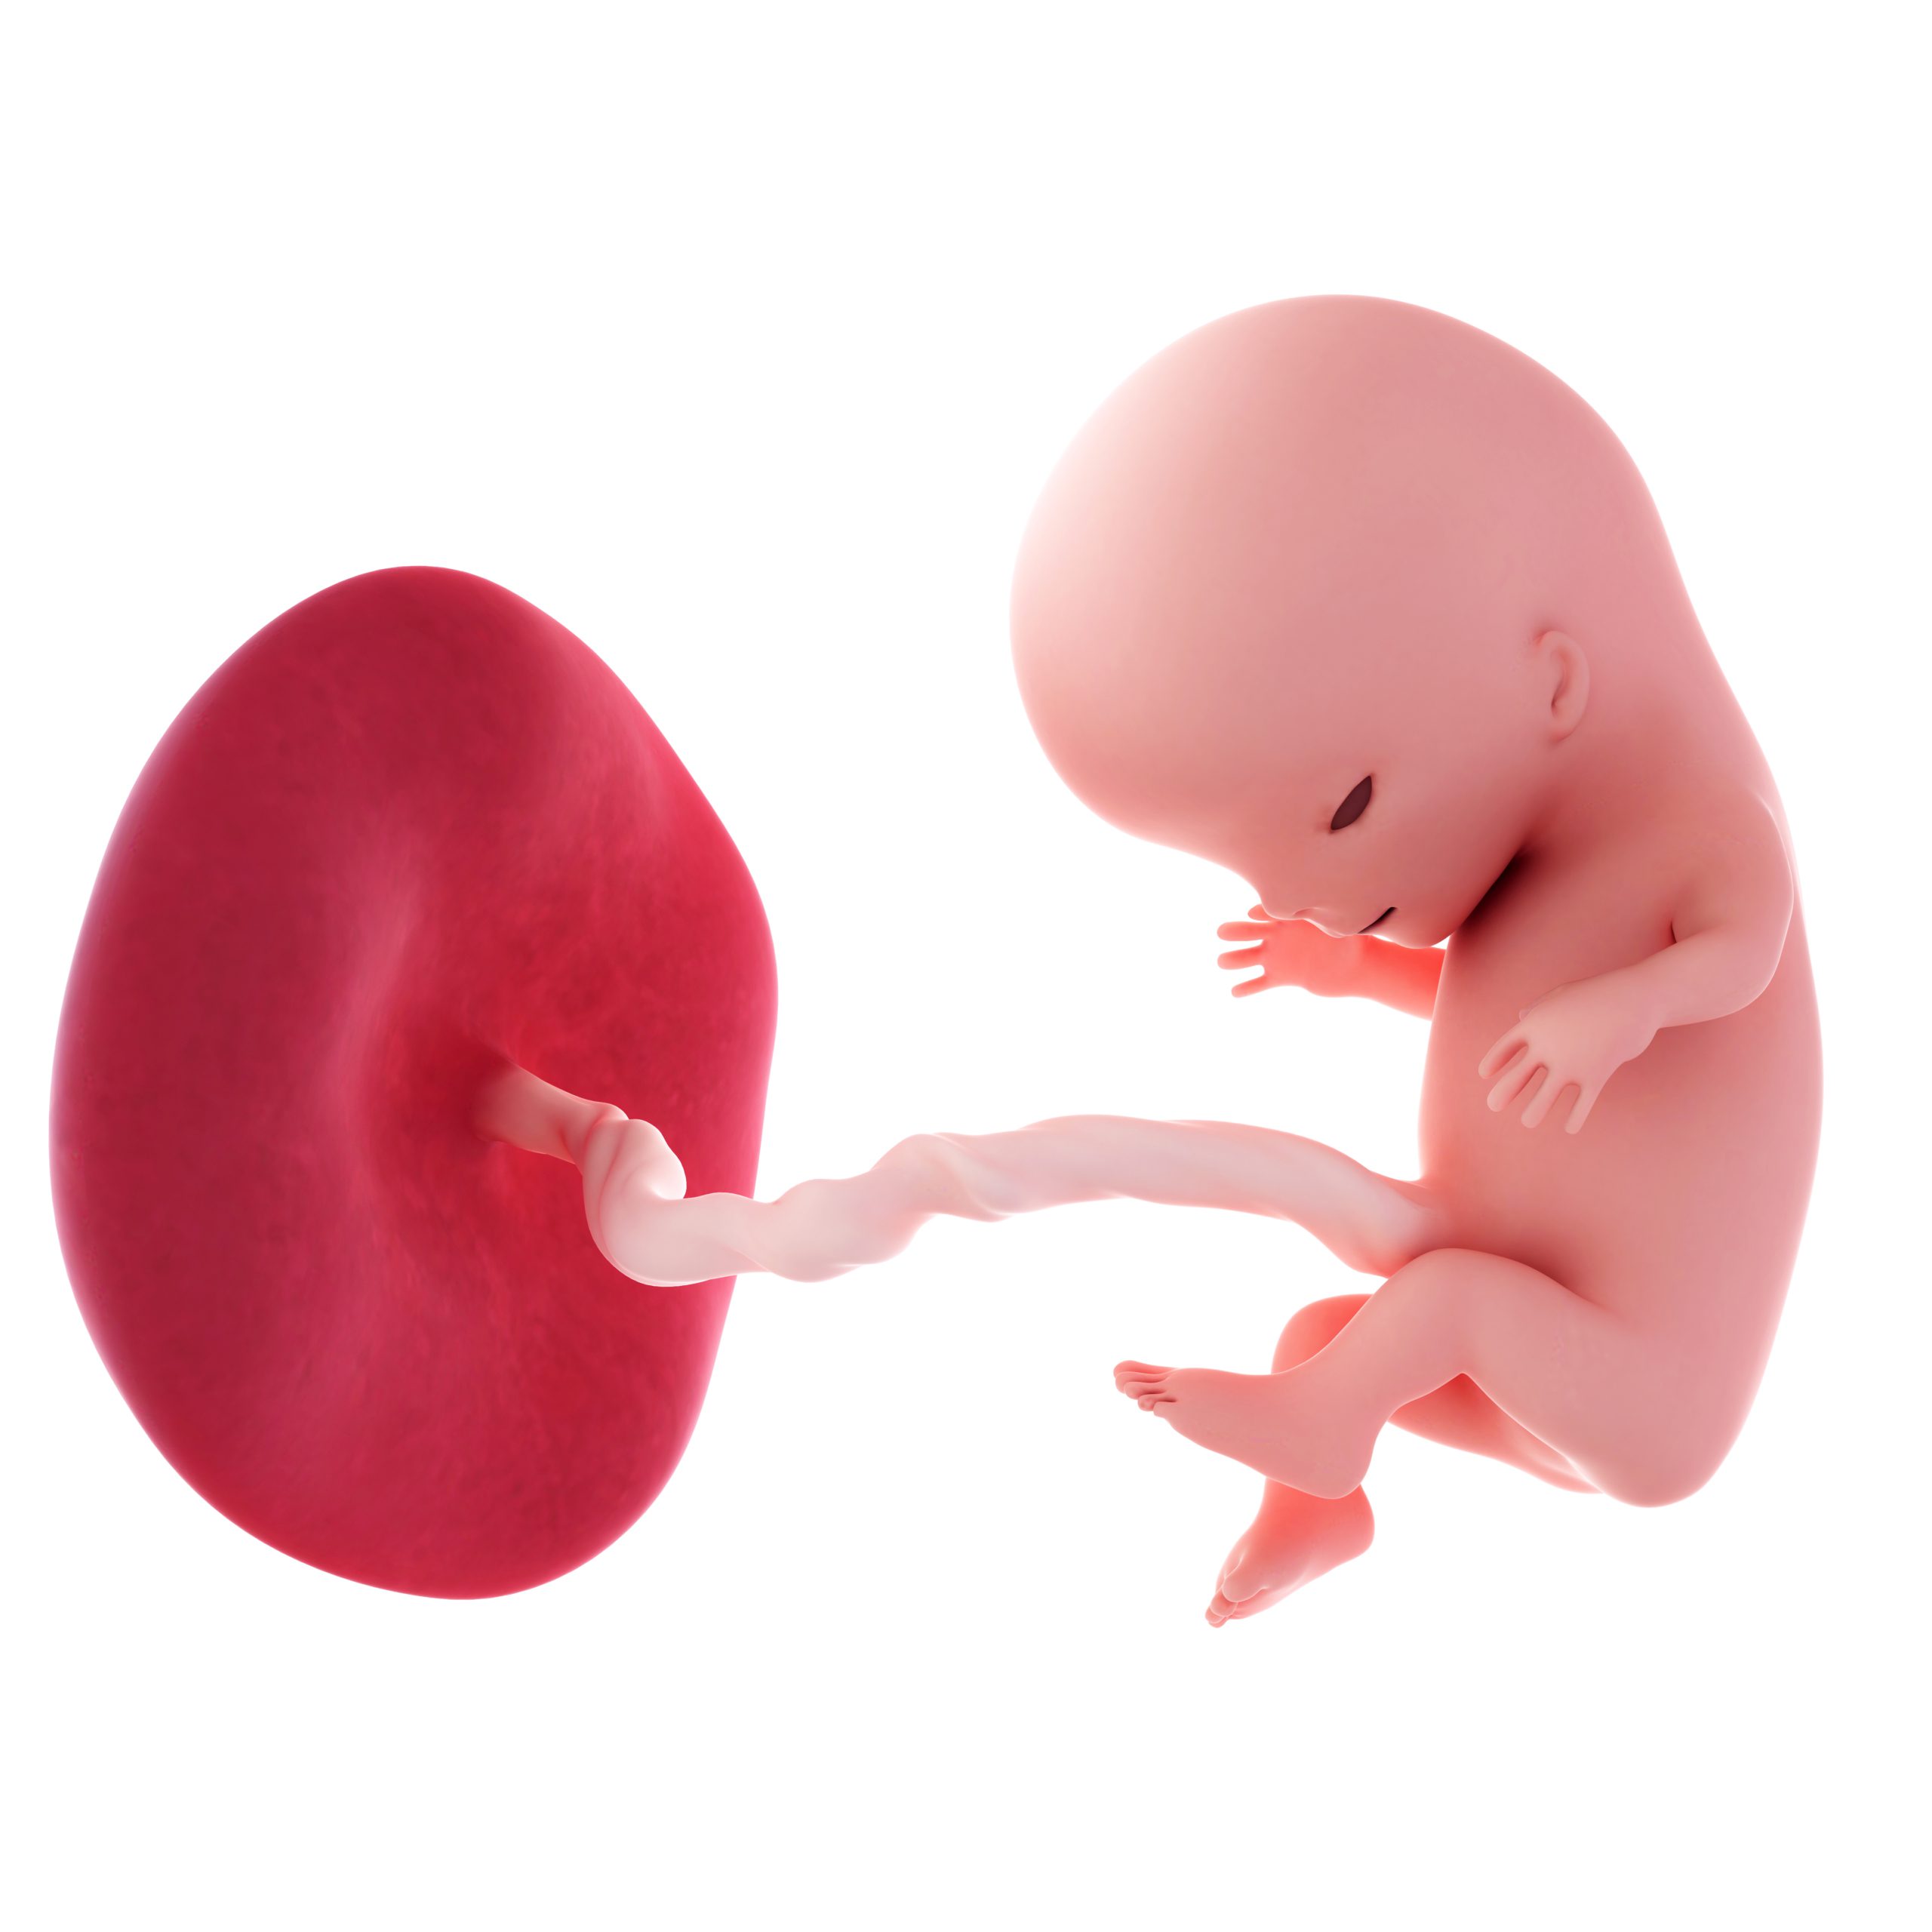

Symbolbild

„,Der Föt… Ihr Baby ist jetzt draußen.’“

Im Krankenwagen selbst waren die Schmerzen mal mehr mal weniger. Der Sanitäter gab mir über die Vene Schmerzmittel. Anschließend setzte er sich neben mich und hielt meine Hand und sagte mir, dass ich das super mache und nun drücken sollte. Ich drückte. Das kostete mich sehr viel Kraft – Kraft, die ich kaum mehr hatte. Und dann, mit einem Mal, spürte ich einen größeren Klumpen. Nach meiner Einwilligung schaute der Sanitäter nach und sagte dann: „Der Föt… Ihr Baby ist jetzt draußen.“ In diesem Moment habe ich meine Augen geschlossen und ausgeatmet.